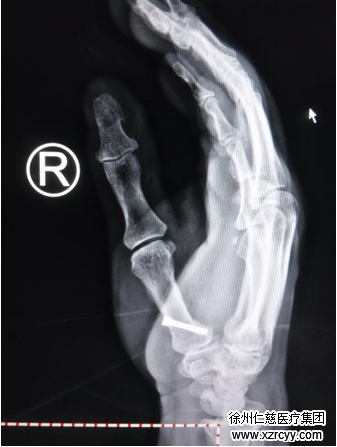

术后